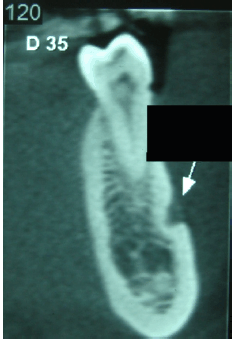

Observando a imagem abaixo, marque a alternativa que corresponde ao diagnóstico radiográfico (seta):

Enunciado 2830311-1